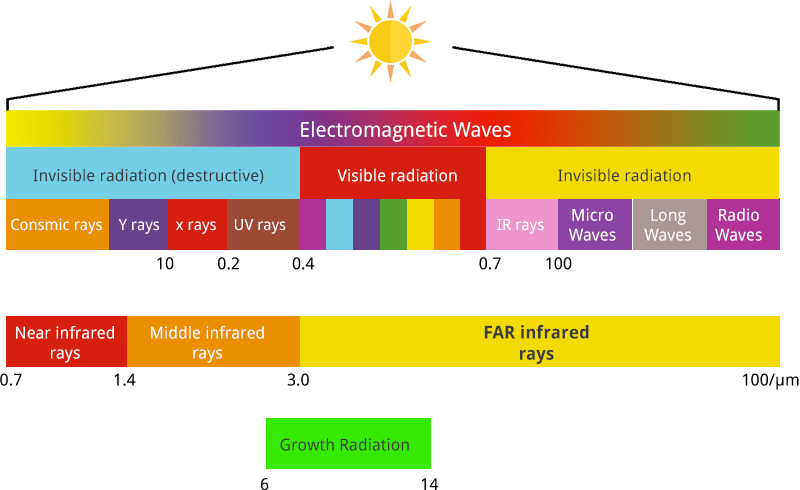

Infrared radiation (IR), also called infrared light, is electromagnetic radiation (EMR) with wavelengths longer than those of visible light. IR wavelengths extend from the nominal red edge of the visible spectrum at 0.7 micrometers or microns (frequency 430 THz), to 1 millimeter (300 GHz).

6 – 14 Micron bandwidth essential to grow of living things

Far Infrared (FIR)

Far infrared (FIR) radiation is an IR subdivision of the electromagnetic spectrum and has wellness effects, mostly within the sub-range of roughly 3-12µm (biological window).

Far Infrared/IR-C 3.0– 1000 μm